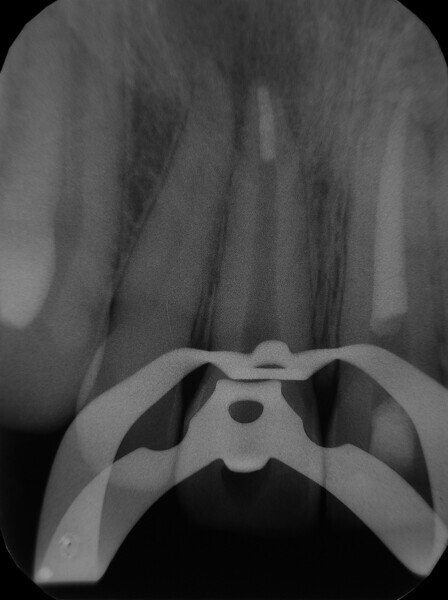

Irrigating the root canal: A case report